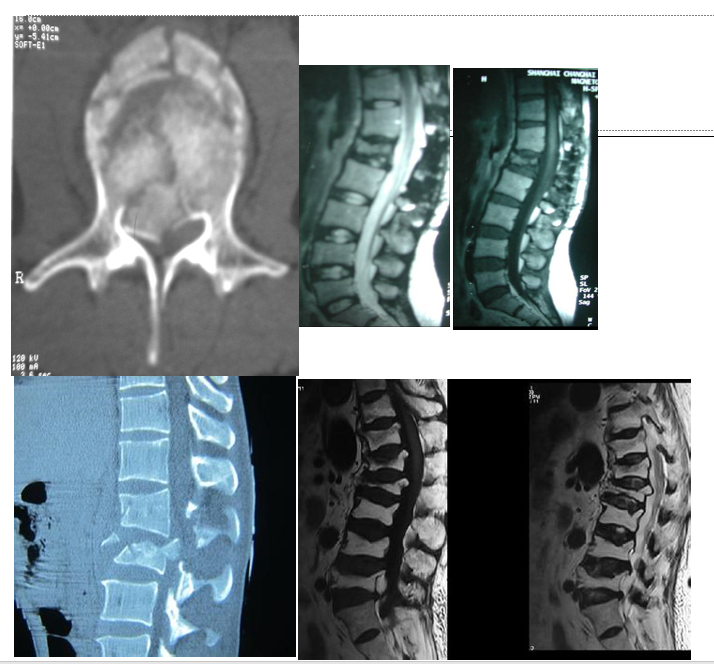

X线片上往往不能判断脊柱骨折处于骨质愈合的哪个阶段多椎体的骨折可能发生于不同时期,并非每个被压缩椎体都是责任椎体,需要手术治疗MRI在判断骨折椎体是否愈合及选择手术椎体时起重要作用急性期或亚急性期(2-30天之间的骨折):T1WI呈低信号, T2WI呈高信号晚期(30天以后):T1WI和T2WI上表现等信号。

当椎体T1WI、T2WI无信号改变,即使X线片椎体有压缩改变,亦说明椎体骨折已愈合,椎体已处于稳定状态,为非责任椎体,可不予治疗。相反对于X线片椎体无明显压缩,但MRI有显著信号改变者应考虑为责任椎体,予以手术。